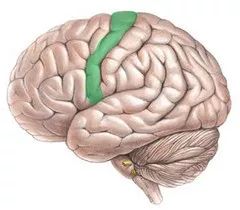

额叶还负责你身体的运动,额叶最上面的一带,是你的运动皮质。

接着是顶叶(parietal lobe) ,顶叶控制触觉,这一部分功能主要在体感皮质实现,体感皮质在运动皮质旁边。

运动和体感皮质很有趣,因为它们和人体的对应关系非常工整。神经科学家清哪楚地知道每个皮质的各部位分别对应身体的那些部分,下面我们要放出本文中最奇怪的一张图:何蒙库鲁兹(homounculus)

何蒙库鲁兹由神经外科医生Wilder Penfield创造,用来呈现运动和触感皮质如何对应到人体部位。图中的人体部位越大,代表运动和触感皮质中有越多的部分是与该部位对应的。这张图有一些有趣的点:

首先,皮质中负责脸和手的运动和触感的部分,比全身其它部分加起来都要大。当然这不难想通,人脸需要能做出各种微妙的表情,而手需要能够无比的灵巧。而身体的其它部位,比如肩膀、膝盖、背部,在移动和触感上可以粗糙很多。所以人们用手指,而不是脚趾,来弹钢琴。

其次,运动和触觉皮质各自对于不同身体部位的分配比例基本是一致的。也就是说人体中越是需要灵活运动的部位,也越是触觉最灵敏的。